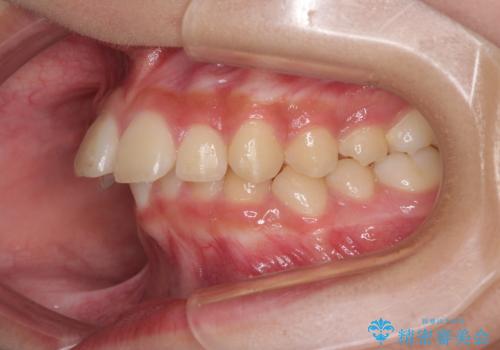

- 前歯の叢生と深い咬み合わせを気にして来院された患者様です。

奥歯の咬み合わせを見ると、上顎が下顎に対して相対的に前方にありました。

深い咬み合わせを改善するためには、上顎臼歯を後方に移動させつつ、下顎の小臼歯を直立させる必要があります。